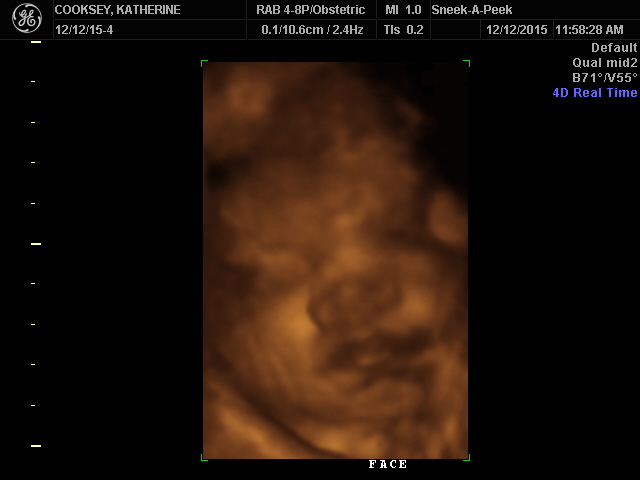

3rd Tri Ultrasound Sharing

Re: 3rd Tri Ultrasound Sharing